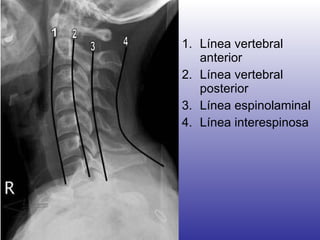

Imagenología Rx cervical lateral  ¿Cuello en flexión? > 3 mm de separación entre el diente del odontoides y el arco anterior del axis Línea espinolaminar hacia posterior en C2

Línea vertebral anterior Línea vertebral posterior Línea espinolaminal Línea interespinosa

Imagenología Rx cervicallateral ¿Cuello en flexión? > 3 mm de separación entre el diente del odontoides y el arco anterior del axis Línea espinolaminar hacia posterior en C2

Línea vertebral anteriorLínea vertebral posterior Línea espinolaminal Línea interespinosa

• #99 ) Anterior vertebral line 2) Posterior vertebral line 3) Spinolaminal line 4) Interspinous line.